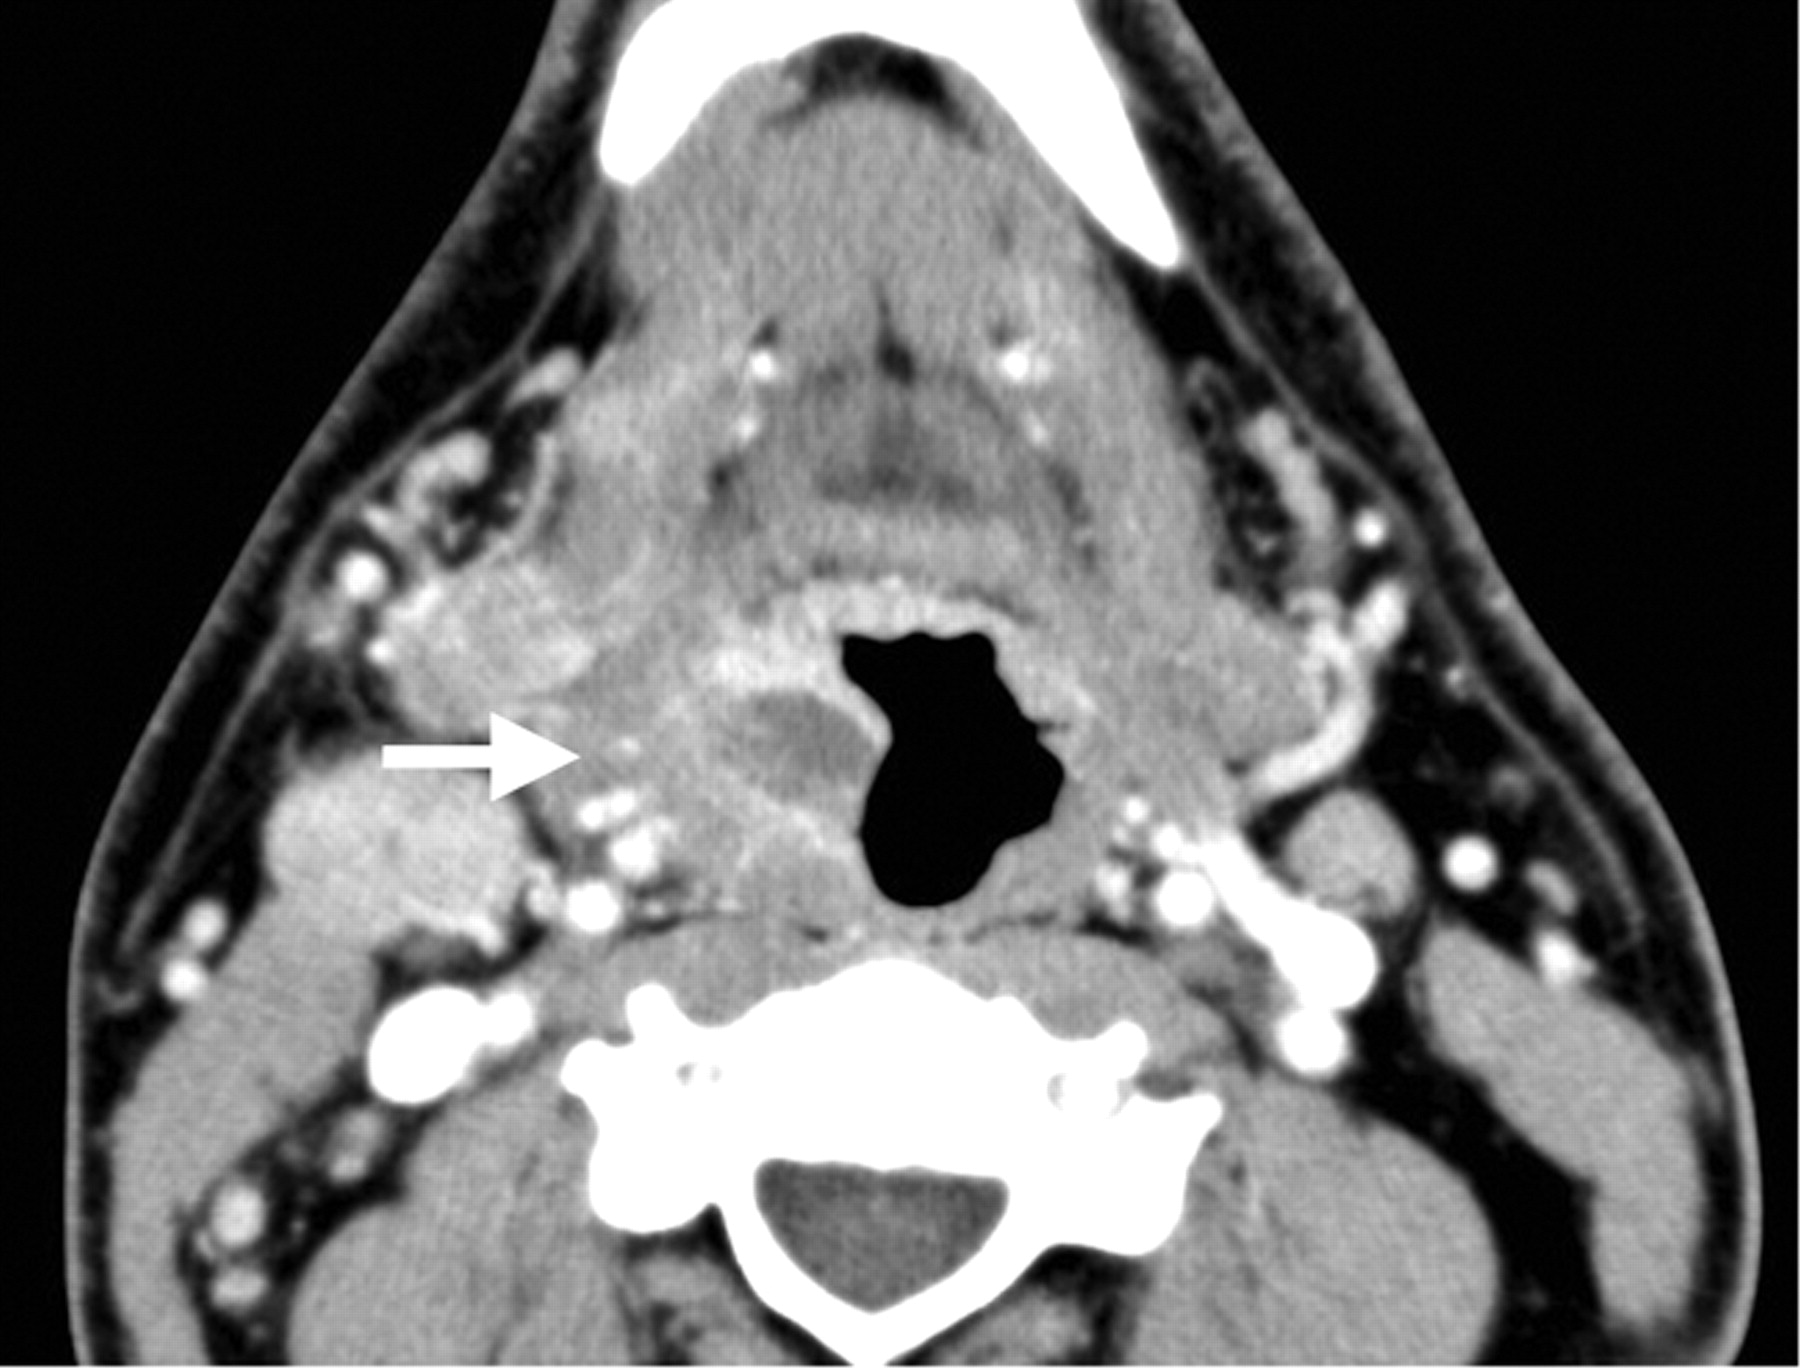

Otalgia is an infrequent symptom of nasopharyngeal cancer, but some sources describe its presence in as many as 14% of patients.8 The usual presentation is a neck mass from metastatic adenopathy, conductive hearing loss, and bloody nasal discharge.25 Cross-sectional imaging will reveal a mass in the lateral pharyngeal recess, often accompanied by metastatic cervical lymphadenopathy (Fig 9).25

Squamous cell carcinoma of the nasopharynx. Axial CT scan with contrast demonstrates an abnormal soft-tissue mass with relatively uniform contrast enhancement filling the left lateral fossa of Rosenmueller, affecting the pharyngeal plexus of cranial nerve IX.